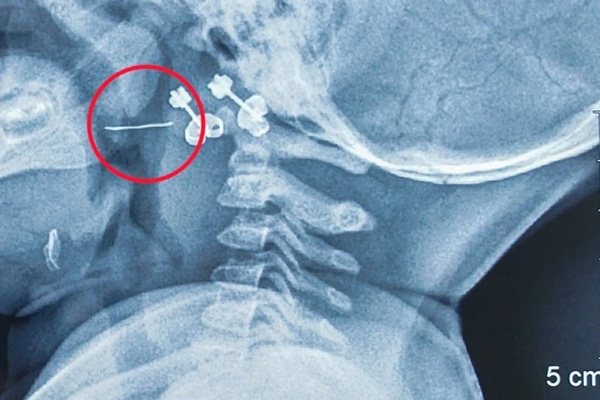

14/10/2022 23:01Sợi thép của rây lọc cháo ăn dặm đâm xuyên qua amidan của bé gái 13 tháng

Ngày 14/10, Bệnh viện Nhi Trung ương cho biết, các bác sĩ khoa Tai - Mũi - Họng vừa can thiệp gắp thành công dị vật là sợi thép dài 2 cm đâm xuyên amidan trái của bệnh nhi 13 tháng tuổi ở Nam Định.

Kết quả chụp X-quang cổ ngực phát hiện dị vật kim loại vùng sàn họng - miệng, được chuyển ngay đến Bệnh viện Nhi Trung ương.

Bác sĩ Nguyễn Khắc Trưởng, khoa Tai - Mũi - Họng, Bệnh viện Nhi Trung ương, người trực tiếp gắp dị vật cho bệnh nhi cho biết: "Dị vật là sợi thép nhọn mắc ở vị trí phức tạp, nguy cơ chảy máu cao. Vì thế, ngay khi làm các xét nghiệm cần thiết, bệnh nhi được chuyển đến phòng mổ, gây mê và tiến hành gắp dị vật. Sợi thép được lấy ra chỉ 2cm nhưng rất cứng và nhọn 2 đầu".

Bệnh nhi bị nôn ra máu do sợi thép này đâm xuyên từ cực trên xuống cực dưới amidan bên trái của trẻ.

"May mắn là dị vật chưa xuống sâu hơn nên không gây nguy hiểm đến tính mạng của trẻ. Nếu không được gắp ra kịp thời, đoạn kim loại này có thể gây nhiễm trùng và chảy máu, dẫn đến những hậu quả khó lường", BS Trưởng thông tin trên Dân Trí.

Dị vật nguy hiểm nói trên được xác định là rơi ra từ rây lưới thép để lọc đồ ăn, bị lẫn vào cháo của trẻ trong quá trình chế biến. Hiện tại tình trạng của trẻ đã ổn định và được xuất viện.